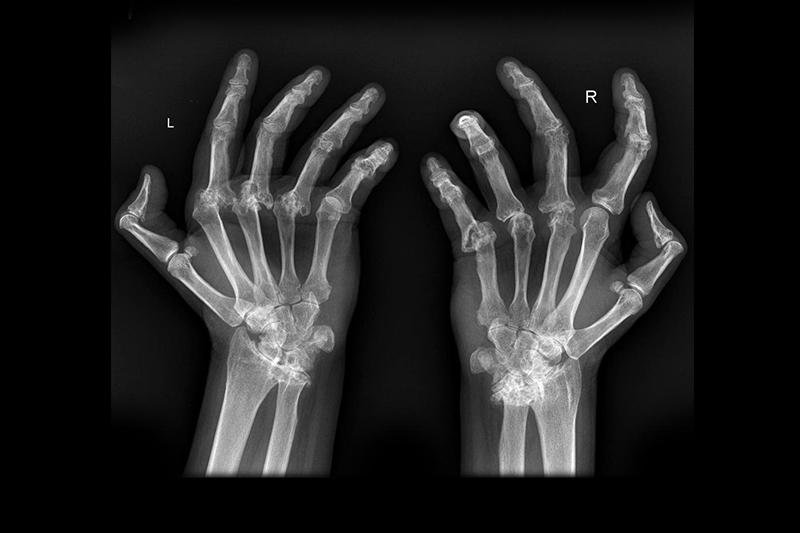

每逢「翻風落雨」,總會風濕發作?常常都聽到身邊的老人家或長輩說,每當天氣轉變,特別是雨天濕氣重,風濕就會發作,膝蓋手肘等關節位置都會隱隱作痛。到底風濕是否真的與天氣有關呢?另外還有種疾病稱作「類風濕關節炎」,與風濕又有何關係呢?

回到大家最關心的問題,到底風濕(退化性關節炎)與天氣有沒有關係呢?事實上,現階段未見有研究或證明天氣會誘發退化性關節炎。而從病因及病徵來看,;都看不出天氣潮濕或下雨都與退化性關節炎或類風濕關節炎有何關係。

但這裡需要重申,並非說所有「老人家風濕」都屬於退化性關節炎,也有可能是類風濕關節炎或其他疾病,因此假如出現病徵,最好還是求醫作詳細診斷才最放心!